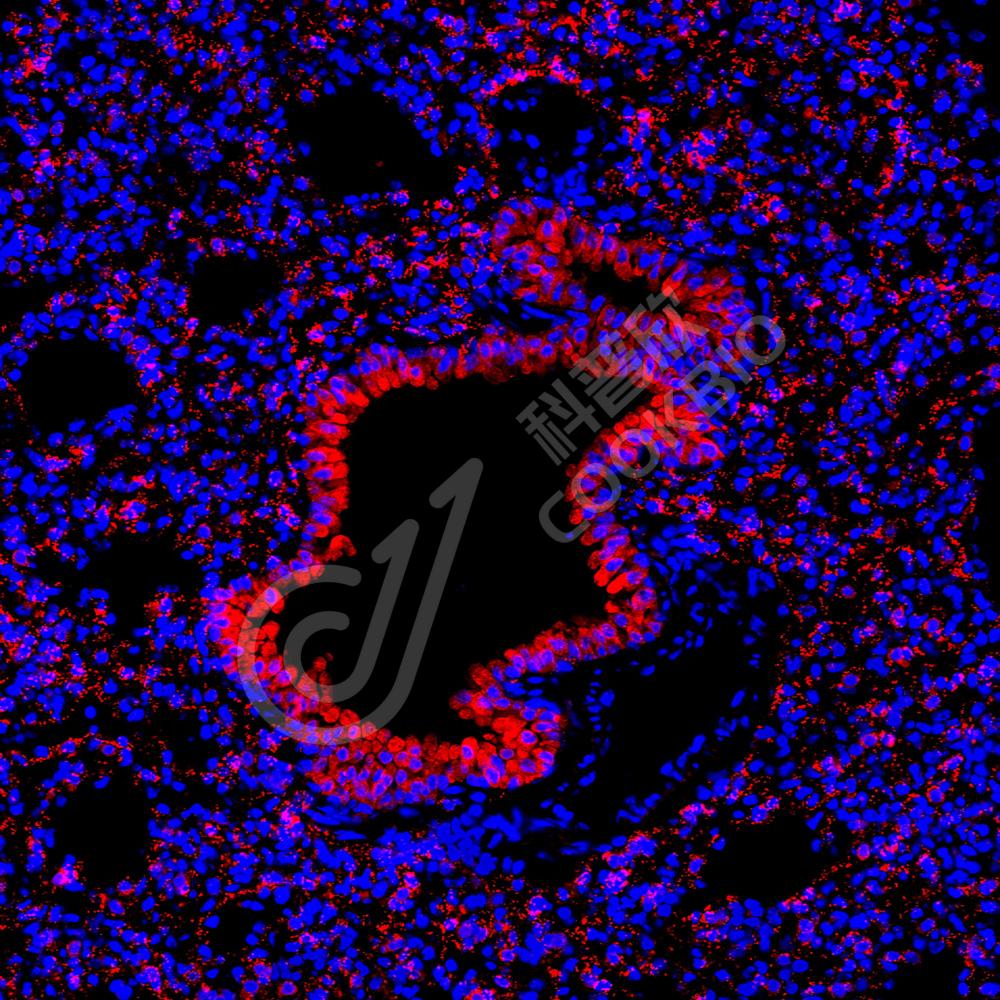

Anti-ErbB2/HER2 兔多克隆抗体

货号: K134797-100

别名: CD340,ERBB2,HER 2,HER 2/neu,HER2,MLN 19,MLN19,NEU,NGL,p185,p185erbB2,Proto oncogene c ErbB 2,Proto oncogene Neu,TKR1,HER-2,erb-b2 receptor tyrosine kinase 2

蛋白质全称 酪氨酸蛋白激酶受体erbB-2

别名 CD340,ERBB2,HER 2,HER 2/neu,HER2,MLN 19,MLN19,NEU,NGL,p185,p185erbB2,Proto oncogene c ErbB 2,Proto oncogene Neu,TKR1,HER-2,erb-b2 receptor tyrosine kinase 2

Uniprot ID P70424

免疫原 小鼠Receptor tyrosine-protein kinase erbB-2重组蛋白